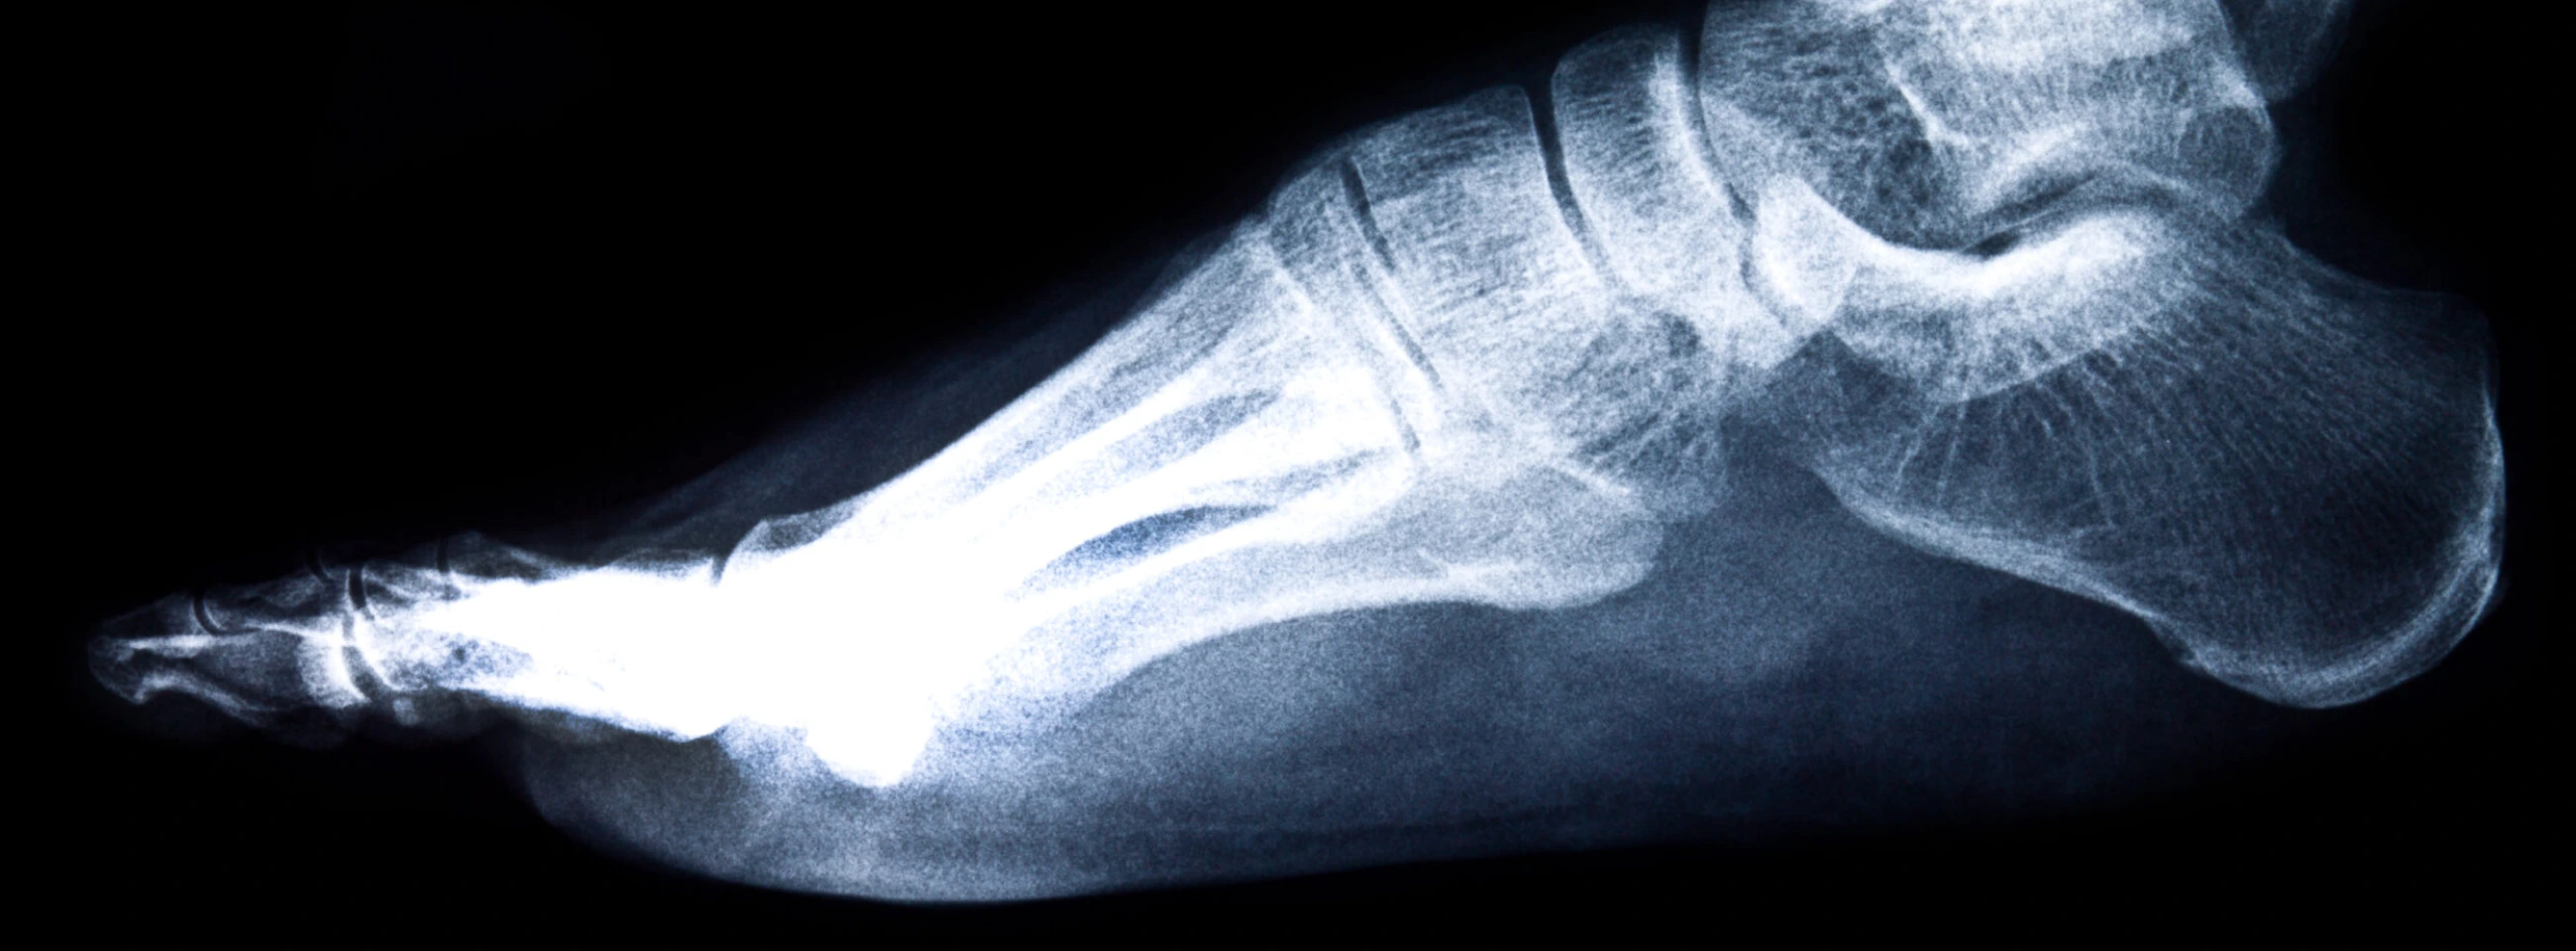

Una radiografía es una técnica que utiliza haces de rayos X para reflejar la estructura interna de los huesos, así como su densidad, tejidos y articulaciones, sin dolor alguno durante el proceso. En el caso de los pies, el especialista podrá analizar los 26 huesos que los constituyen, bien sea por lesiones, traumatismos o golpes, o para evaluar condiciones si se sufre de enfermedades como osteoporosis.

Los pies se consideran estructuras complejas debido a su composición ósea y el número de músculos, ligamentos y tendones asociados. Los huesos denominados falanges son un total de 14 piezas que constituyen los dedos. Además están los metacarpianos con 5 unidades y después el tarso, donde se ubica el talón y todas las conexiones hacia el tobillo.

Un médico puede solicitar que te realices una radiografía de pie para observar en las imágenes obtenidas de una manera clara cualquier daño ocurrido, y así decidir el tratamiento idóneo.